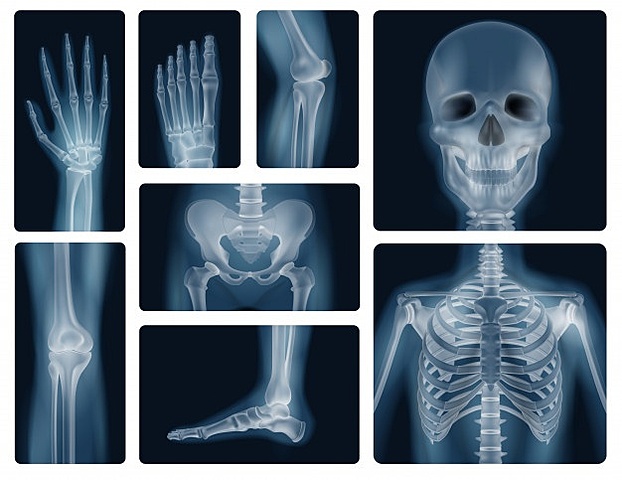

• Radiología Digital

Radiología Digital

F. Mouyens creó el primer sistema de radiología digital directa que produce imágenes de calidad. Un detector de pantalla convierte directamente el patrón de energía de rayos X en señales eléctricas.